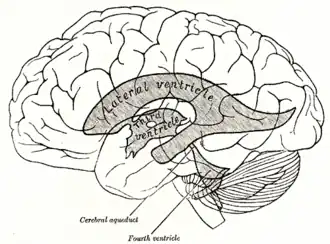

| Drawing of the lateral and third ventricles of the brain. Periventricular leukomalacia involves death of the white matter surrounding the lateral ventricles in fetuses and infants. (Image from Gray's Anatomy, 1918 edition) | |

Periventricular leukomalacia (PVL) is a form of white-matter brain injury, characterized by the necrosis (more often coagulation) of white matter near the lateral ventricles.[1][2] It can affect newborns and (less commonly) fetuses; premature infants are at the greatest risk of neonatal encephalopathy which may lead to this condition. Affected individuals generally exhibit motor control problems or other developmental delays, and they often develop cerebral palsy or epilepsy later in life. The white matter in preterm born children is particularly vulnerable during the third trimester of pregnancy when white matter developing takes place and the myelination process starts around 30 weeks of gestational age.[3]